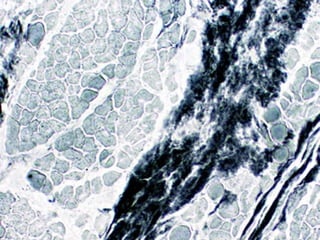

• #6 SILVER STAIN showing black axons surrounded by washed out fat (myelin)

• #7 MYELIN stain showing the REVERSE of the previous slide. If you flip back and forth between this pic and the previous one, it will be like overlaying the negative of a film over the positive.